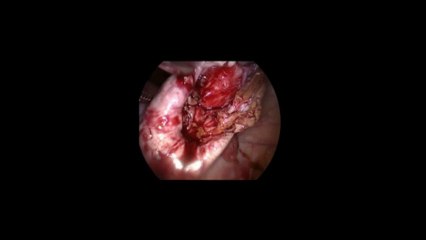

br br br br Laparoskopi yöntemi ile çikolata kisti (endometrioma, endometriozis) ameliyatının ayrıntılarını Prof. Dr. Cem Turan'ın videosundan izleyin. İlk olarak karın içi, rahim ve yumurtalıklar gözleniyor. Yumurtalıklardan (over) biri daha büyük izleniyor. Yumurtalık tutulup, koter ile çiziliyor ve erimiş çikolataya benzer sıvı boşalıyor. Yumurtalık üzerindeki açıklık makasla büyültülüyor, Çikolata kistinin kapsülü (duvarı) sağlam yumurtalık duvarından soyularak çıkartılıyor, Kalan kist duvarı ve kanama alanları bipolar koter ile az miktarda yakılıyor.